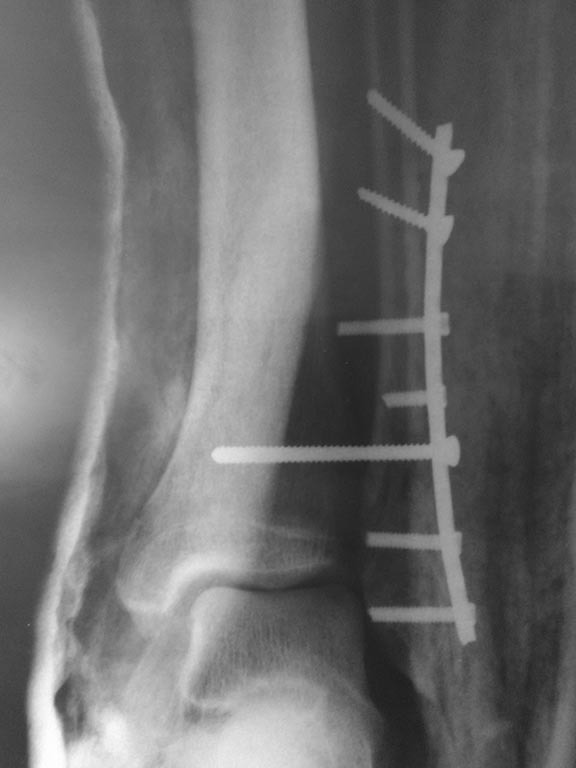

на следующий день

Моё мнение, что ничего переделывать не нужно. Подвывиха стопы кнаружи у пациента нет. Есть подвывих кзади, так как пластинка лежит по передней поверхности малоберцовой кости, а синдесмозный винт выталкивает таранку кзади. Может через 2-2.5 мес после операции удалить винт, а может после нагрузки без удаления винта подвывих кзади устранится.

Коллеги! Вы о чем? Лодыжка фактически не фиксирована (1 винт не в счет при таком расположениии пластины). М/б притянута куда-то к передним отделам "позиционником" - если хотите убедиться сделайте КТ и посмотрите сканы через вырезку. Мое мнение - срочно все это разбирать. Синтезировать н/лодыжку пластиной в противоскользящем положении. затем тестировать синдесмоз. А уж потом размышлять - нужно ли его фиксировать и если да - то чем.

Перелом надсиндесмозный. Лодыжка фиксирована все-таки 2 винтами. а вот синдесмозный винт вроде бы стоит уже в переломе и просто прижимает пластину к большеберцовой кости. на счет реостеосинтеза даже не знаю, но вроде бы послеоперационные снимки сделаны с небольшим вальгусом стопы. Есть ли снимки в нейтральной позиции стопы?

Если внимательно посмотреть снимки, один из винтов, удерживающих пластину, совершенно точно упёрся в большеберцовую (он даже полностью не погружён в блокирующее отверстие). Скорее всего он отодвинул фибулу. Позиционный винт лишь зафиксировал такую позицию. Можно поменять винт на короткий и перепровести позиционный малоинвазивно, ИМХО. С уважением!

Комментировать остеосинтез не буду. Но просто хочу напомнить, что существует такой инструмент как измеритель глубины каналов. ,,Позиционник'' не должен ничего прижимать. Положение пластины на малоберцовой кости в этом случае желательно - заднее (опорная, противоскользящая) Не знаю, делался ли hook test? В моем видении передняя межберцовая связка д.б. цела -по характеру линии перелома наружной лодыжки. В этом случае зачем позиционный винт? Был ли поврежден медиальный комплекс (порции дельтовидной связки)? Надо ли что-то сейчас делать? Не знаю. Надо взвесить много факторов. Желаю удачи авторам в общении с пациентом.T

Я бы переделал. Считаю, что подвывих есть. Наружная лодыжка сильно короткая и находится совсем не в своей вырезке (отсюда и передний ещё подвывих). Гипсом (как на последнем снимке) ситуацию не выправишь, потому что гипс когда-нибудь придётся снять, и всё вернётся, куда и должно, в соответствии с биомеханикой. Верить в то, что с удалением винта всё станет на свои места, я бы тоже не стал. Такое возможно при передавливании синдесмоза, да. Но тут совсем другие проблемы. Если у Вас всё ещё есть сомнения, сделайте КТ - и всё увидите.